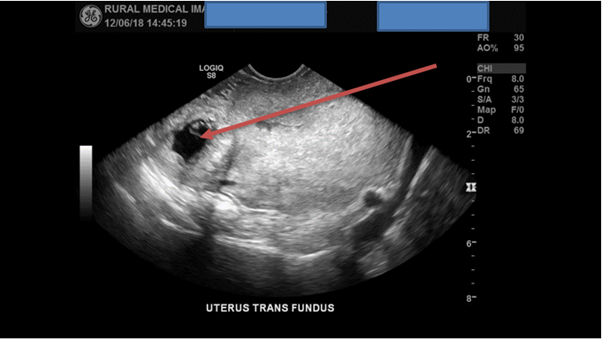

A scan of the left adnexa in the transverse plane from inferior to superior concluded that no pathology was detected but failed to observe the left ovary. A second sweep now of the right adnexa observed a well-defined anechoic lesion near the interstitial fallopian tube region. A possible GS was suspected, no obvious yolk sac or foetal pole was detected within the lesion. Literature states that the risk of an EP can exceed 90% when there is no detectible IUP and there is a corresponding adnexal lesion present. [1]

Figure 3: TAS detects a well-defined anechoic lesion observed near the right interstitial fallopian tube region, highly suspected of being an EP.

A superior scan in transverse plane of the right adnexa confirms the presence of a single GS with a possible internal foetus present. Although the initial first image was of suboptimal quality the HD zoom function was utilised for the next images for improved image optimisation and for confirmation of a possible live foetus. The angle of the TV probe was moved more inferiorly to place the pathology into the centre of the screen improving the FOV.

With the HD zoom function now enabled and an improved FOV multiple images of diagnostic quality were now acquired which confirmed that a right interstitial single EP was present. Three CRL’s were acquired totalling an average length of 7mm.